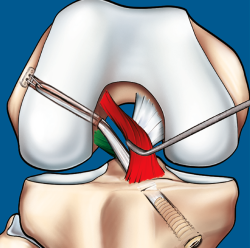

Figura 9. Esquema que ilustra el tratamiento con plastia de reconstrucción unifascicular posterolateral.

La reconstrucción selectiva del fascículo afectado sigue los principios básicos de la reconstrucción clásica anatómica del LCA (Figuras 9 y 10). Los autores realizan 3 portales: un portal anterolateral, lo más proximal posible con el fin de evitar la almohadilla grasa infrapatelar de Hoffa y tener una visión panorámica de toda la articulación; un portal AM alto y parapatelar, que utilizaremos como portal de visión y que nos va a permitir una mejor visualización de la huella anatómica femoral; y un portal AM accesorio, lateral al cóndilo femoral medial e inmediatamente superior al menisco interno, desde donde realizaremos el brocado del túnel femoral mediante técnica de manos libres(8). Otros autores recomiendan la realización del túnel femoral mediante técnica outside-in, considerando que ello facilita la realización del brocado femoral sin dañar las fibras del fascículo intacto(4).

Figura 10. Plastia de reconstrucción selectiva unifascicular (fascículo posterolateral –PL–). A: imagen artroscópica de la rodilla izquierda desde el portal anterolateral. Se evidencia una rotura completa crónica del fascículo PL con remanente tibial (flecha) e integridad del fascículo anteromedial (AM); B: imagen artroscópica de la rodilla izquierda desde el portal anterolateral. Colocación de la guía tibial tomando el remanente como referencia en una reconstrucción selectiva del fascículo PL; C: imagen artroscópica desde el portal AM que muestra la plastia de reconstrucción selectiva-aumentación del fascículo PL con autoinjerto de isquiotibiales (flecha).